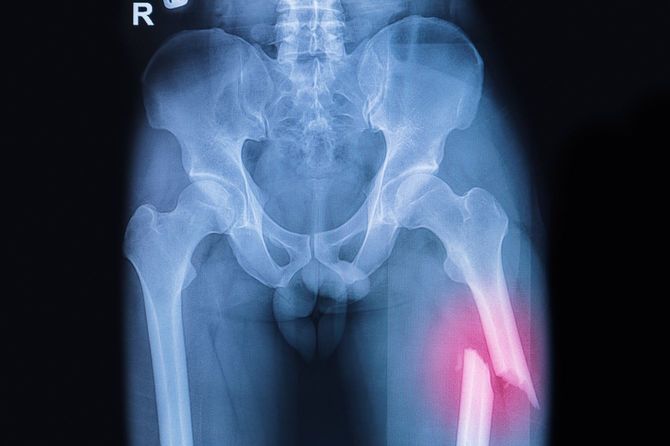

大木さんは慌てて救急車を呼び、搬送先の病院で、左側の大腿骨を骨折していることがわかった。母親は、脳梗塞の後遺症の片麻痺で右手が上げられず、左手はつえをついていたにもかかわらず、「あれは、クリの木ね」と言って右手で指さして転倒したと施設は説明。

「転倒後、施設側は、母がトイレ誘導時に立てない状態にあったので、リハビリパンツを着用し、車いすでトイレ介助をしたとのことですが、立てなかった時点でなぜ施設内に医師がいるにもかかわらず診せなかったのか。また、15時のおやつの際に車いすに移乗するとき、右ひざを曲げると痛みの訴えが聞かれたとのことですが、なぜこの時の右膝の痛みの訴えから、医師に診せる必要があると判断しなかったのか……。疑問でなりません」